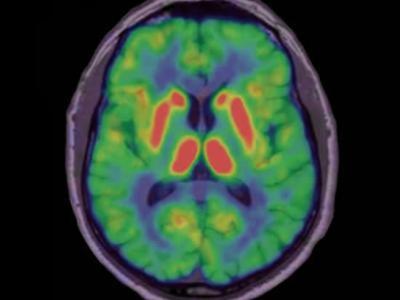

5-羟色胺解决了数十年之久的帕金森氏病之谜

健康大脑的PET图片 据6月30日的《科学 - 转化医学》杂志报道说,一项对2名接受了...